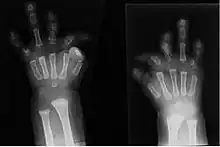

Radiographie montrant un cas sévère de brachydactylie

La brachydactylie est un terme de médecine signifiant : brièveté d'un ou de plusieurs doigts. C'est une caractéristique dont la transmission génétique est généralement autosomique dominante[1],[2].la brachydactylie est de 5 types de A à E et cinq sous types de A1 à A5.